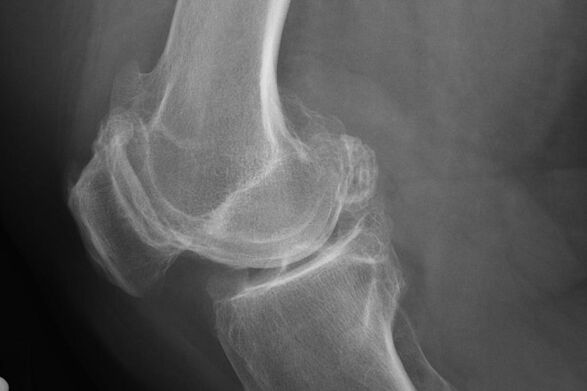

X -RAY aiuta a identificare le deviazioni nella cartilagine.

Dopo l'esame, il medico prescrive la radiografia del paziente. Questo è il metodo principale per diagnosticare l'artrosi dell'articolazione del ginocchio di qualsiasi grado.

X -Ray dà al medico un'idea dei cambiamenti nella cartilagine dell'articolazione. In alcuni casi, tuttavia, la fase iniziale non può essere definita nell'immagine.

Se necessario, il medico può prescrivere un passaggio ripetuto di una radiografia o di una risonanza aritmetica e magnetica.